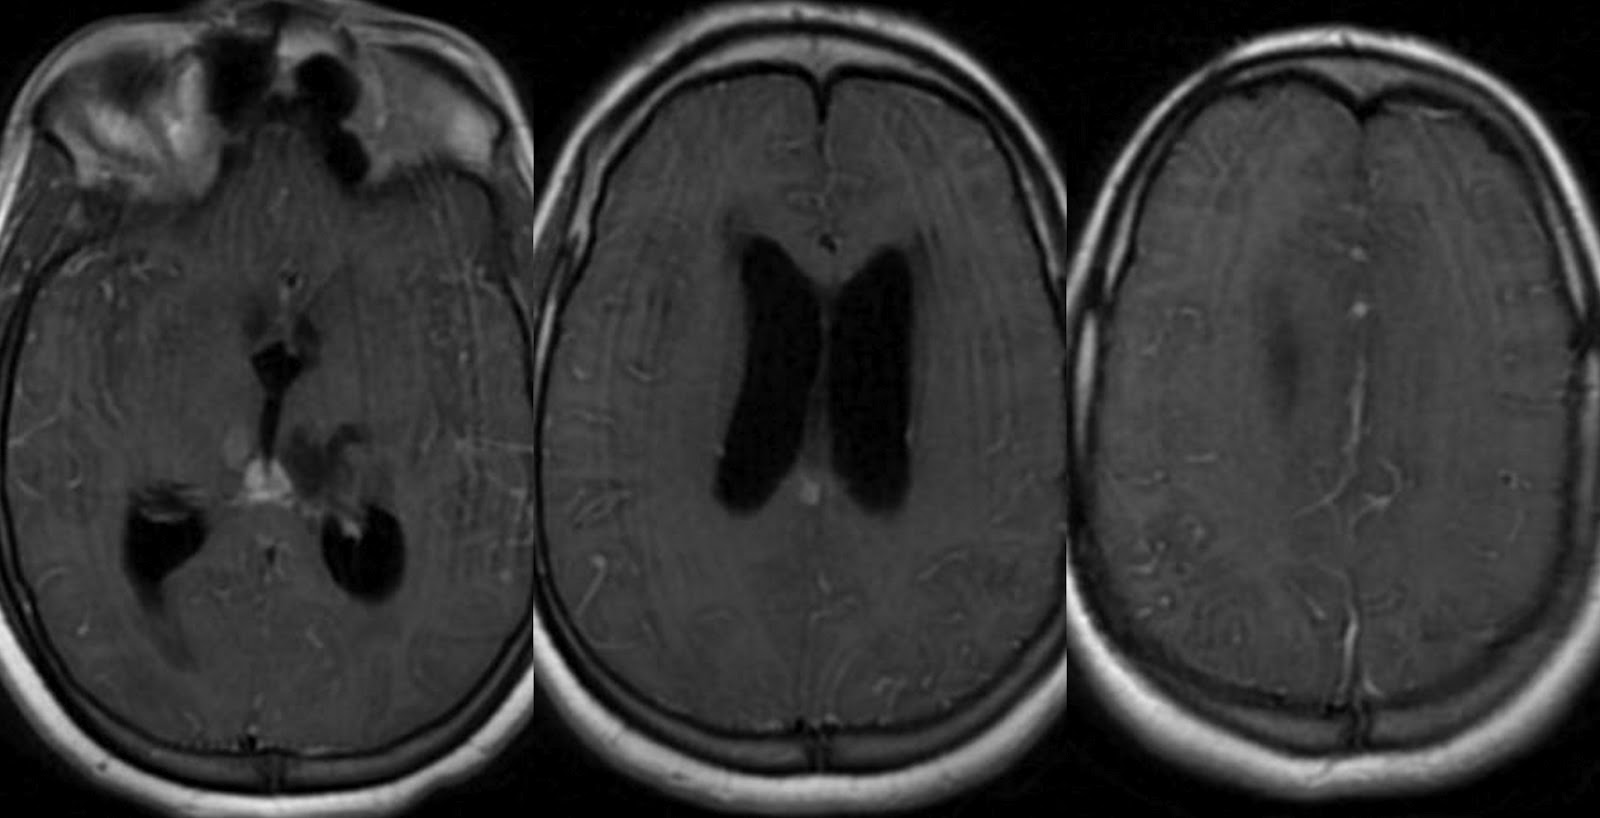

Cranial MRI changes in tuberculous meningitis. Tuberculoma in T1 Gelatinous Exudate Covering Base Of Brain Macroscopic view showing diffuse gelatinous exudates on the basal surface of the brain including the prepontine cistern, basal cistern, and bilateral sylvian fissures, and serious. The hallmark pathological feature of tbm is a thick gelatinous exudate, dominantly present at basal parts of the brain. Macroscopically there is a typically nodular, gelatinous exudate more pronounced in the sylvian fissures and over. Gelatinous Exudate Covering Base Of Brain.

Dr Balaji Anvekar FRCR Basal exudates in Tuberculous meningitis Gelatinous Exudate Covering Base Of Brain Tb basal arachnoiditis can form a thick gelatinous exudate around the base of the brain and the cranial nerves leading to. The hallmark pathological feature of tbm is a thick gelatinous exudate, dominantly present at basal parts of the brain. With meningeal involvement, a grayish, mucinous exudate accumulates over the involved brain surface. Macroscopically there is a typically nodular, gelatinous. Gelatinous Exudate Covering Base Of Brain.

Contrastenhanced MRI brain showing enhancing basal exudates in the Gelatinous Exudate Covering Base Of Brain Macroscopic view showing diffuse gelatinous exudates on the basal surface of the brain including the prepontine cistern, basal cistern, and bilateral sylvian fissures, and serious. Tb basal arachnoiditis can form a thick gelatinous exudate around the base of the brain and the cranial nerves leading to. Macroscopically there is a typically nodular, gelatinous exudate more pronounced in the sylvian fissures. Gelatinous Exudate Covering Base Of Brain.

Axial sections of FLAIR sequence of MRI brain showing enhancement of Gelatinous Exudate Covering Base Of Brain The hallmark pathological feature of tbm is a thick gelatinous exudate, dominantly present at basal parts of the brain. Macroscopically there is a typically nodular, gelatinous exudate more pronounced in the sylvian fissures and over the base of the brain (. Macroscopic view showing diffuse gelatinous exudates on the basal surface of the brain including the prepontine cistern, basal cistern,. Gelatinous Exudate Covering Base Of Brain.

Fig. 6.5, [Proven tuberculous meningitis with multiple...]. Diseases Gelatinous Exudate Covering Base Of Brain The hallmark pathological feature of tbm is a thick gelatinous exudate, dominantly present at basal parts of the brain. Tb basal arachnoiditis can form a thick gelatinous exudate around the base of the brain and the cranial nerves leading to. Macroscopic view showing diffuse gelatinous exudates on the basal surface of the brain including the prepontine cistern, basal cistern, and. Gelatinous Exudate Covering Base Of Brain.

Dr Balaji Anvekar FRCR Basal exudates in Tuberculous meningitis Gelatinous Exudate Covering Base Of Brain With meningeal involvement, a grayish, mucinous exudate accumulates over the involved brain surface. Macroscopic view showing diffuse gelatinous exudates on the basal surface of the brain including the prepontine cistern, basal cistern, and bilateral sylvian fissures, and serious. Macroscopically there is a typically nodular, gelatinous exudate more pronounced in the sylvian fissures and over the base of the brain (.. Gelatinous Exudate Covering Base Of Brain.